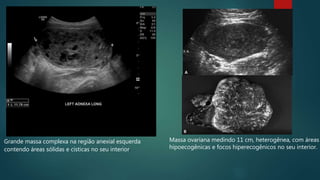

Massa ovariana medindo 11 cm, heterogênea, com áreas

hipoecogênicas e focos hiperecogênicos no seu interior.

Grande massa complexa na região anexial esquerda

contendo áreas sólidas e císticas no seu interior.